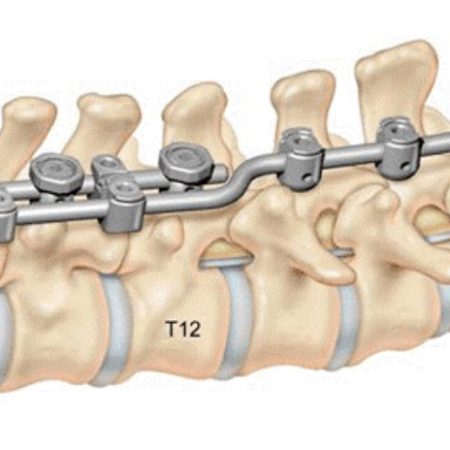

EXPEDIUM Vertebral Body Derotation System